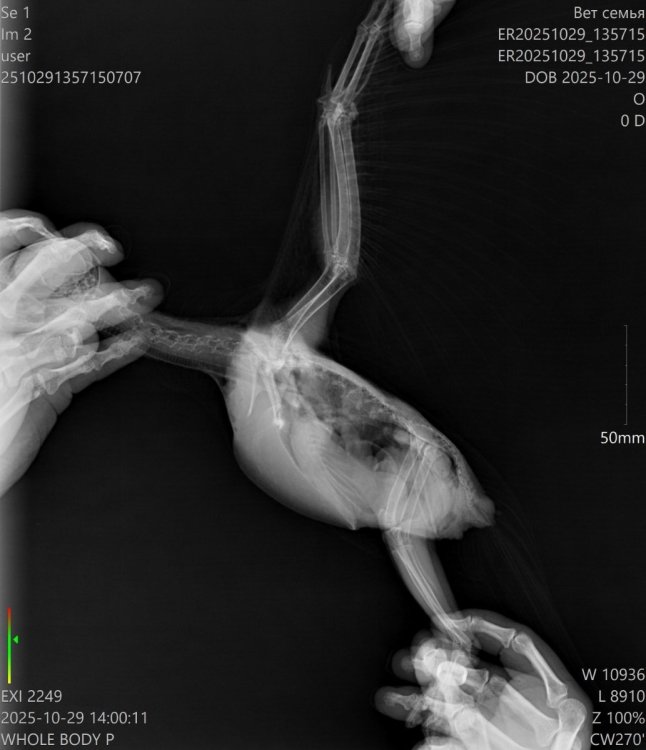

Добрый вечер!!! Ситуация такая, попугай жако 7 месяцев, внезапно заболел, перестал есть, сидит весь вжался в себя. Кормили всегда одним и темже кормом РИО, воду часто меняли, клетка убиралась часто, в доме тепло, ел фрукты и овощи каждый день. Отвезли на стационар в клинику, сделали снимки, врач кормил его через катетор, он с трудом ел, помета почти небыло и весь тресся, кололи ему антибиотики. К сожалению наша птичка вчера умерла. Хотя 3 дня назад была очень активная, играла и общалась. Помогите пожалуйста определить по снимкам что на этих снимках, есть ли какие серьезные отклонения.

ER20251029_135715_ER20251029_135715__29-10-2025 14_00_11_1-2 (1).jpg

ER20251029_135715_ER20251029_135715__29-10-2025 13_59_01_1-1.jpg